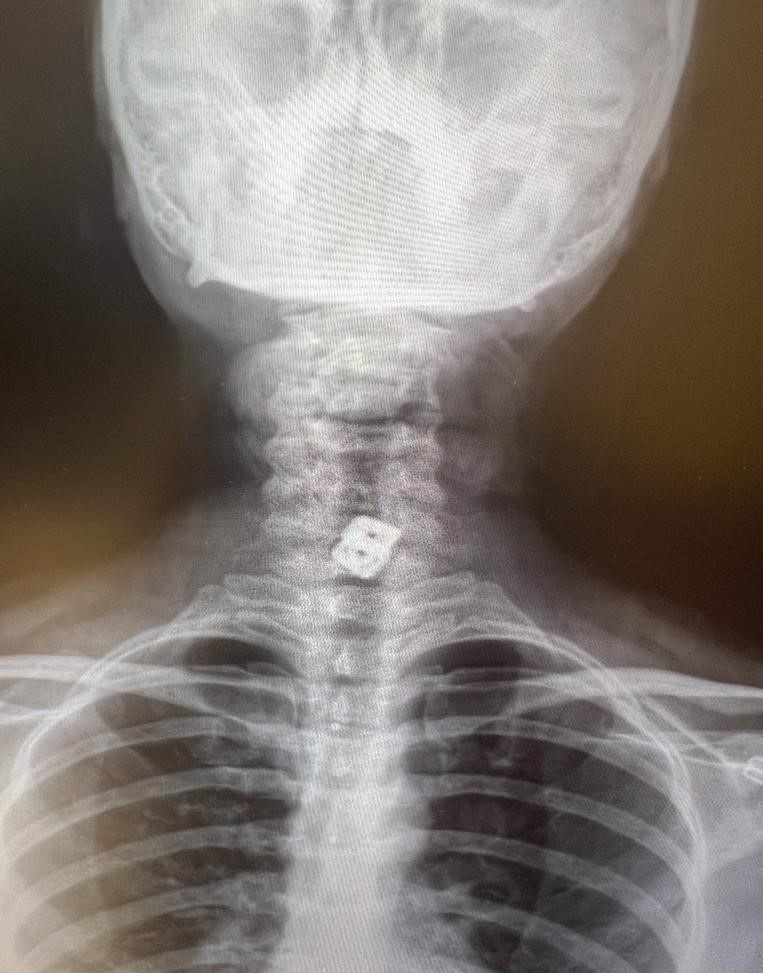

“O hastanede beyin ve sinir cerrahisi uzmanı tarafından ameliyata alınan Sultan Tıraş’ın boyun omuruna konulan iki aparattan biri çıkarılmış, ancak diğerinin yemek borusunu delip mideye indiği belirlenmiş.

Bu ciddi bir sorun olup, hayati riski yüksektir. En hızlı şekilde tıbbi tedaviye başladık, gastroenteroloji bölümümüzde endoskopi yapıldı. Yemek borusunda oluşan delik ve delikten mideye inen metalik cerrahi aparat görüldü. Göğüs kafesi içinde ciddi bir iltihap ve hava birikimi vardı.

“Endoskopi sırasında hastanın midesinde metalik bir oluşuma benzer yabancı cisim ile yemek borusunda ülser görünümü izledik. Lezyon bölgesi belirlendikten sonra hastamızın tedavisi için Göğüs Cerrahisi Bölümümüze durumu ilettik. Prof. Dr. Levent Elbeyli Hocamız hastamızın sağlığına kavuşması için gerekli tedaviyi planlayarak, başarılı bir operasyonla sonuca ulaştı. Emeği geçen herkese teşekkür ediyorum. Hastamızı sağlıklı bir ömür diliyorum.”